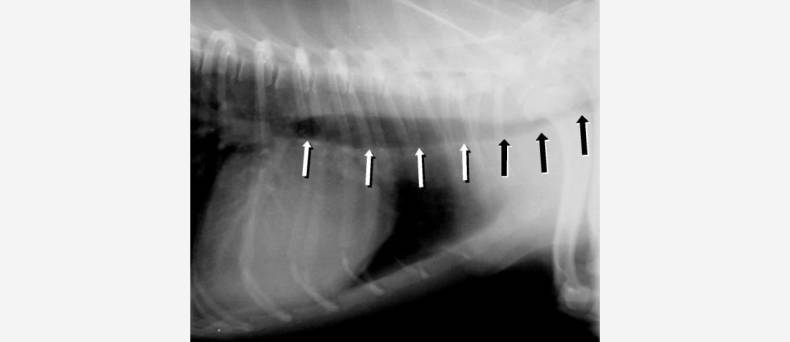

Katten kunnen lijden aan een aantal ziekten aan de luchtwegen of bronchiën. Hiertoe behoort o.a. bronchitis. Deze ziekte kan voorkomen bij katten van alle leeftijden.

De kat heeft een droge hoest, afgewisseld met aanvallen van krampachtig hoesten. In ernstige gevallen moet de kat door zijn bek ademen in plaats van door zijn neus.